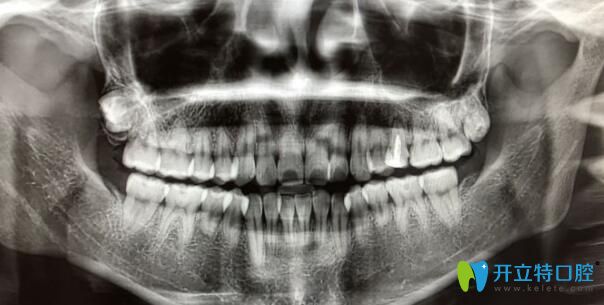

案例二:牙根短做正畸5個月自白

其實(shí)做正畸之前,我也非常擔(dān)心,但是變美的沖動大于一切,所以在認(rèn)真的篩選了和醫(yī)生之后,我開始了我的正畸之旅。

牙根短做正畸5個月自白

我已經(jīng)戴牙套5個月了,下個月還要打種植釘,而且迄今為止都比較好。

牙根短做了牙齒矯正

到現(xiàn)在我還是不后悔。沒有覺得牙齒有松動。為自己悄悄變美每天都很高興。